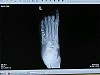

I checked which hospital was on my insurance plan and we headed over to nearby Alvarado Medical. When I finally got my xrays taken, they confirmed that I had four broken metatarsals. The smallest one was fragmented. The one next to it was offset and ultimately trying to secede from itself. The final two were snapped but still touching. Well, I didn't need an xray to tell me my foot was bad off, but at least I could verify that this was no case of hypochondria.

So I called up Dr. Sharon Dreeben's office. She's not so slothlike as to vacation on President's Day and upon hearing that I had a broken foot, her office scheduled me to come in that day. Just after I got my foot xrayed, the xray technician mumbled, "Wow." I said, "Looks good, huh?" He said that there was no way I was hobbling around on crutches just for attention. I said as I thumped my chest with a closed fist, "No sir, this is from the heart."

Back in the examination room I got wrapped back up and they scheduled me for surgery on Thursday. Chris snapped a few digital shots of my xray so I'd have something to share on the internet.

Metatarsal 1 on the far left has two screws in it and will remain there. Metatarsal 2 has a pin sticking through it. Metatarsal 3 has an absorbable rod in it. Metatarsal 4 has the other pin sticking through it. Metatarsal 5 is living life large because nothing happened to it. I hear it taunt the other bones every night.